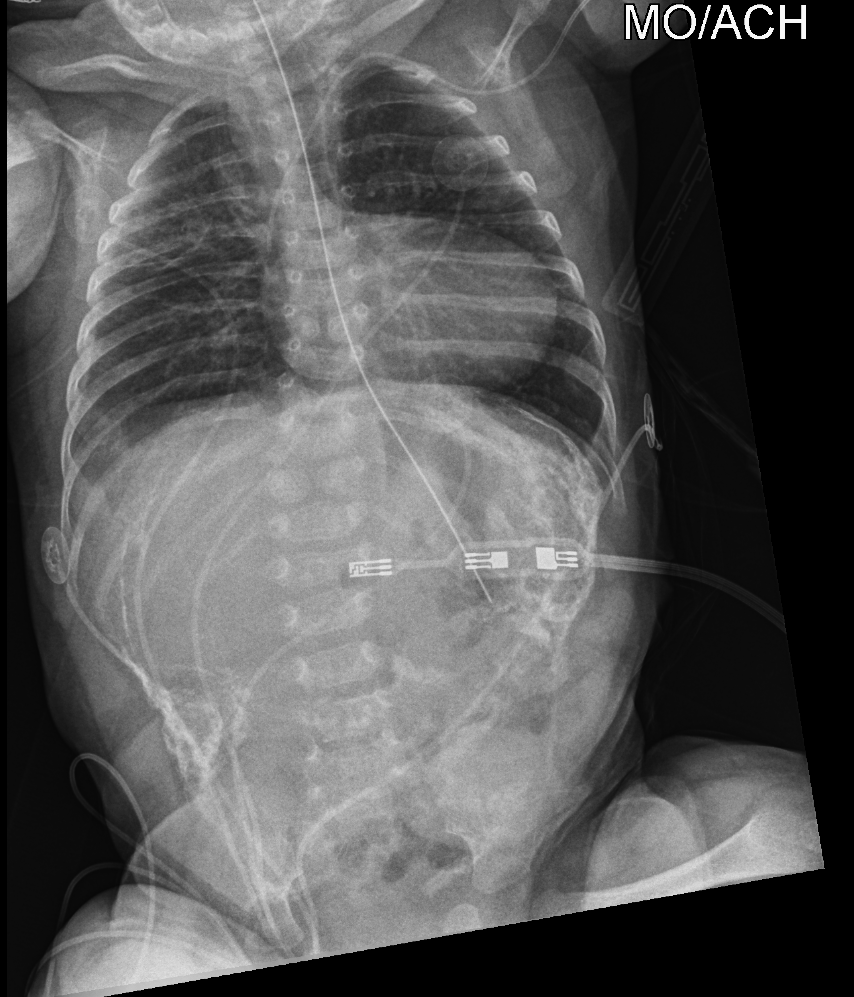

Info Images Findings Impression Reco/Acuity Case Images View Images / Launch Visage Case Notes History 2 month old suspected of being a victim of physical child abuse. No history of trauma, patient presents with subdural hematoma and rib fractures. Exam Skeletal survey Prior Study none Dicom View Reference Material

Section 1 Submit Findings CB1546 Findings Skeletal Survey - Technique Check Skull AP/Lat Yes No Cervical and Thoracolumbar spine Yes No Chest X-Ray Yes No Ribs – Left/Right Oblique Yes No Abdominal X-Ray Yes No Pelvis with both hips Yes No Bilateral Humerus, Forearm, Hand Yes No Bilateral Femur, Tibia/fibula, feet Yes No Any additional lateral views of the extremities Yes No The exam is over or under penetrated. Yes No The exam may or may not be limited by overlying structures or soft tissues, body habitus, patient positioning, support devices, or motion. Yes No The area of concern is indicated by the patient, technologist, or care provider. Yes No The area of concern is included on the exam. Yes No Soft Tissues There is soft tissue swelling, indistinctness of fat/muscle planes, gas, or laceration in the area of clinical concern. Yes No There is an effusion, fat pad displacement, or fat fluid level. Yes No There is a radiodense or lucent foreign body. Yes No There are other densities, calcifications, post-surgical changes, or support devices in the soft tissues. Yes No Any support lines/tubes. Yes No Bone There is a break or interruption of the continuity of the cortical or cancellous bone. Yes No There is overriding of the trabeculae with apparent sclerosis. Yes No There is displacement of a fracture fragment. Yes No There is bowing of the bone in addition to the fracture at the apex of the bowed bone concerning for the greenstick. Yes No There is a spiral fracture of the leg concerning for toddler’s fracture. Yes No There is abnormal angulation or bulging of the cortical surface relative to the normal cortex which could be from a buckle or torus fracture. Yes No There is a displaced fragment which may be from avulsion by a tendon, ligament, or joint capsule or from a comminuted or other fracture. Yes No The stress trabeculae or other trabeculae of the cancellous bone are interrupted or otherwise abnormal. Yes No There is subperiosteal or endosteal reaction which could indicate a healing or subacute fracture or other abnormality. Yes No There is hard/soft callus formation. Yes No There is remodeling of the bone. Yes No There is a corner fracture or metaphyseal lesion that could be from nonaccidental trauma. Yes No There are multiple fractures of different ages. Yes No There are vertebral body/spinous process fractures. Yes No There are rib fractures. Location - posterior or lateral. Yes No There is scapular/sternal fracture. Yes No There are fractures of the digits. Yes No There are wormian bones. Yes No There are intrasutural bones. Yes No There is metaphyseal abnormality (lucencies, increased density, erosion) which may be from something other than injury such as stress, metabolic disease (e.g. rickets with loss or distortion of the zone of the provisional calcification), neoplasm (e.g. leukemia), heavy metals, inflammation, or infection. Yes No There are metaphyseal spurs. Yes No There are bony deformities involving multiple bones. Yes No The bones are gracile. Yes No There are non-healing fractures. Yes No There is/are focal or multifocal lytic/lucent, blastic/sclerotic or mixed density lesion(s) or other abnormality. Yes No Overall bone density is increased or decreased with or without thinning or thickening of the cortical or cancellous bone. Yes No Growth plates, ossification centers, apophyses The growth plate(s) is/are abnormal. Yes No There is widening of the physis from a fracture with or without displacement of the epiphysis (Salter-Harris I). Yes No There is a fracture through the physis which then extends into the metaphysis with or without angulation or displacement (S-H II) Yes No There is a fracture through the physis which then extends into the epiphysis and is intra-articular, with or without angulation or displacement (S-H III). Yes No There is a fracture through the metaphysis, physis, and epiphysis which extends into the joint space with or without angulation or displacement (S-H IV) Yes No There is narrowing of the physis from a compression fracture (S-H V). Yes No The apophysis, epicondyle, secondary ossification center, or accessory ossicle is displaced or otherwise abnormal. Yes No NA The ossification centers are underdeveloped. Yes No Joints and alignment There is an effusion, fat pad displacement, or fat fluid level. Yes No The epiphysis or subchondral bone is fractured, interrupted, flattened, compressed, impacted, displaced, or otherwise abnormal. Yes No There is an intra-articular loose body or chondrocalcinosis. Yes No The joint is widened, narrowed, dislocated, malaligned, or incongruent. Yes No There is pseudoarthrosis. Yes No Other findings There are developmental changes or other anatomic variants or other existing conditions that may or may not be contributing to symptoms which can or should be further evaluated non-emergently or are otherwise incidental. Yes No The remainder of the exam is abnormal for age. Yes No The lungs show focal airspace opacity. Yes No There is pneumothorax. Yes No There is organomegaly. Yes No There is intra-abdominal calcification. Yes No There is displacement of the bowel loops. Yes No There is free intraperitoneal air. Yes No There is paraspinal soft tissue abnormality. Yes No The bowel loops are dilated/obstructed. Yes No